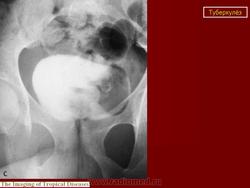

Рентгенологические методы исследования: флюорография (рентгенография) легких, обзорная и внутривенная урография в различных модификациях, томография почек, ретроградная пиелография, цистография, уретроцистопростатография, ангиография и др. Обзорный снимок мочевых путей позволяет обнаружить обызвествления в органах мочеполовой и других систем, изменения опорно-двигательного аппарата (туберкулезный спондилит, метастазы при раке почки и т. п.), определить контуры и размеры почек (увеличение или уменьшение, выбухания, втяжения). По внутривенной урограмме оцениваются функциональное состояние почек и анатомические особенности чашечно-лоханочной системы, мочеточников, мочевого пузыря; урография - основной рентгенологический метод исследования. Соответственно форме и стадии нефротуберкулеза могут быть выявлены; при субклиническом нефротуберкулезе - слабое контрастирование чашечно-лоханочной системы, хаотичное расположение чашечек, их деформация, при папиллите («начальном» деструктивном нефротуберкулезе) - неровность, стушеванность, нечеткость контуров чашечки ввиду наличия признака деструкции, при кавернозном туберкулезе - наличие полостей как в корковом, так и в мозговом слое с неровными, фестончатыми краями; при туберкулезном пионефрозе - изображение увеличенной почки с выбухающими неровными контурами, наличием больших полостей распада, нередко сливающихся между собой, резким снижением либо потерей функции (выключение - аутонефрэктомия); при нефросклерозе (вторично-сморщенная почка) - почка небольших размеров.

Начальный признак специфического поражения мочевых путей - расширение чашечно-лоханочной системы и мочеточника (снижение их сократительной способности в результате токсического воздействия, изменения функционального характера). Во всех случаях «неясной» уретерогидронефротической трансформации врач должен предположить наличие туберкулеза мочевой системы. В дальнейшем обнаруживают различные деформации чашечно-лоханочной системы (с уменьшением ее емкости) с явлениями гидрокаликоза; сужения мочеточника с расширением его выше стеноза; натянутость, четкообразную форму мочеточника; симптом подтянутости стенки мочевого пузыря; уменьшение емкости и различные деформации его контуров вплоть до появления двойного контура - симптома «песочных часов». При восходящей или микционной цистографии, урет-роцистопростатографии выявляют пузырно-мочеточниковый рефлюкс, а при последней - сужения уретры и затекание контрастного вещества в полости предстательной железы. Томографию почек применяют для уточнения контуров почки. Ретроградную пиелографию выполняют при неинформативности внутривенной урографии и для выяснения характера выключения туберкулезного очага (сопоставление пиело- и урографических данных). Ангиография позволяет получить представление об ангиоархитектонике пораженной почки, что важно при определении хирургической тактики.